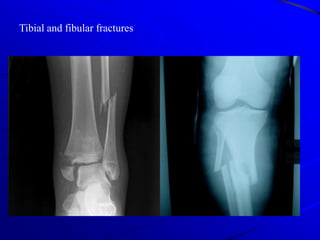

Tibial and fibular fractures

Fracture Tibia & Fibula:- Mechanism :-Direct trauma , falling .        - Management :               - Closed reduction & cast immobilization .               - Open reduction internal fixation by plate                  and screws or inter locking nail .